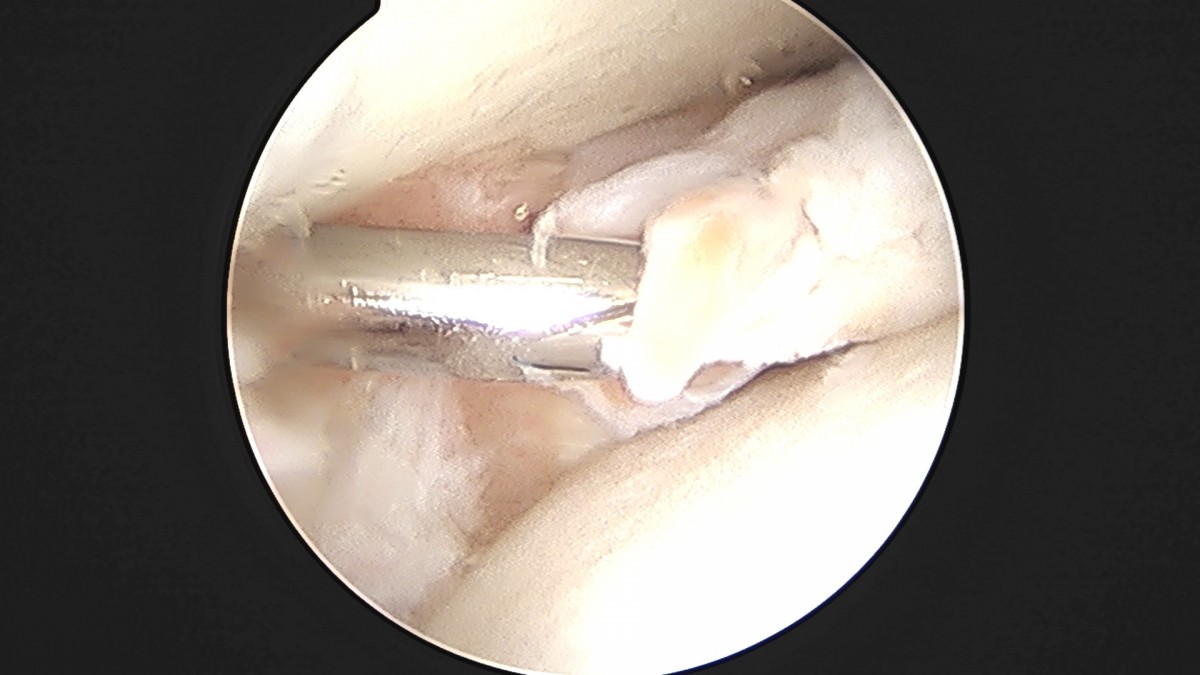

이재상원장님 발목 활액막 절제술 및 인대 봉합술 정보O 환자

dae765e4d9ac96aee867c9d6292d8784_1758003798_9553.jpg